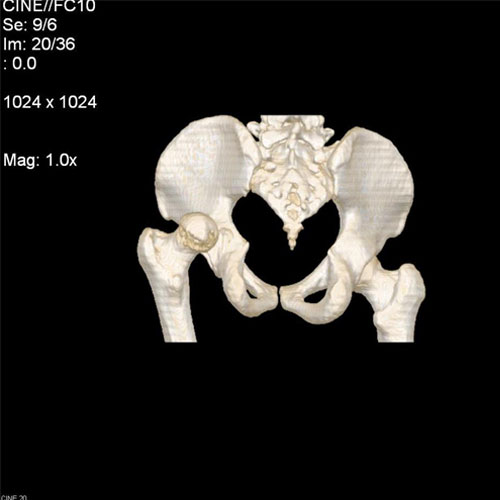

SCAN6

46 year old male, with h/o hip joint pain after epileptic attack. CT with 3D reconstruction of pelvis showing posterior dislocation of hip joint.